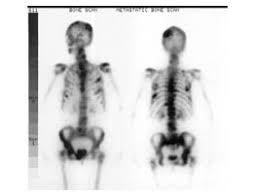

How Do You Know If Breast Cancer Has Spread To Bones : Secondary Breast Cancer In The Lung / We have more about this in our information about controlling symptoms of secondary breast cancer.. Treatment at this stage focuses on controlling the cancer and. But even though it's moved to other organs, it still behaves like. It is similar to a pet scan, but it uses a different radioactive substance that settles in areas of change in the bones. The main symptoms of secondary breast cancer in the bone include: Breast cancer mostly spreads to the bones, lungs, liver, and brain.

It is similar to a pet scan, but it uses a different radioactive substance that settles in areas of change in the bones.